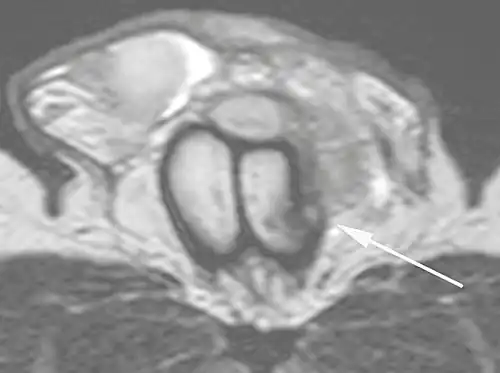

B: Axial T2-weighted turbo spin-echo magnetic resonance imaging scan showing left-sided discontinuity of the tunica albuginea (arrow), secondary to fracture.[2]

Ultrasound examination is able to depict the tunica albuginea tear in the majority of cases (as a hypoechoic discontinuity in the normally echogenic tunica). In a study on 25 patients, Zare Mehrjardi et al. concluded that ultrasound is unable to find the tear just when it is located at the penile base. In their study magnetic resonance imaging (MRI) accurately diagnosed all of the tears (as a discontinuity in the normally low signal tunica on both T1- and T2-weighted sequences). They concluded that ultrasound should be considered as the initial imaging method, and MRI can be helpful in cases that ultrasound does not depict any tear but clinical suspicions for fracture are still high. In the same study, authors investigated accuracy of ultrasound and MRI for determining the tear location (mapping of fracture) in order to perform a tailored surgical repair. MRI was more accurate than ultrasound for this purpose, but ultrasound mapping was well correlated with surgical results in cases where the tear was clearly visualized on ultrasound exam.[10] The advantage of ultrasound in the diagnosis of penile fracture is unrivaled when its noninvasive, cost-effective, and nonionising nature are considered.[11]